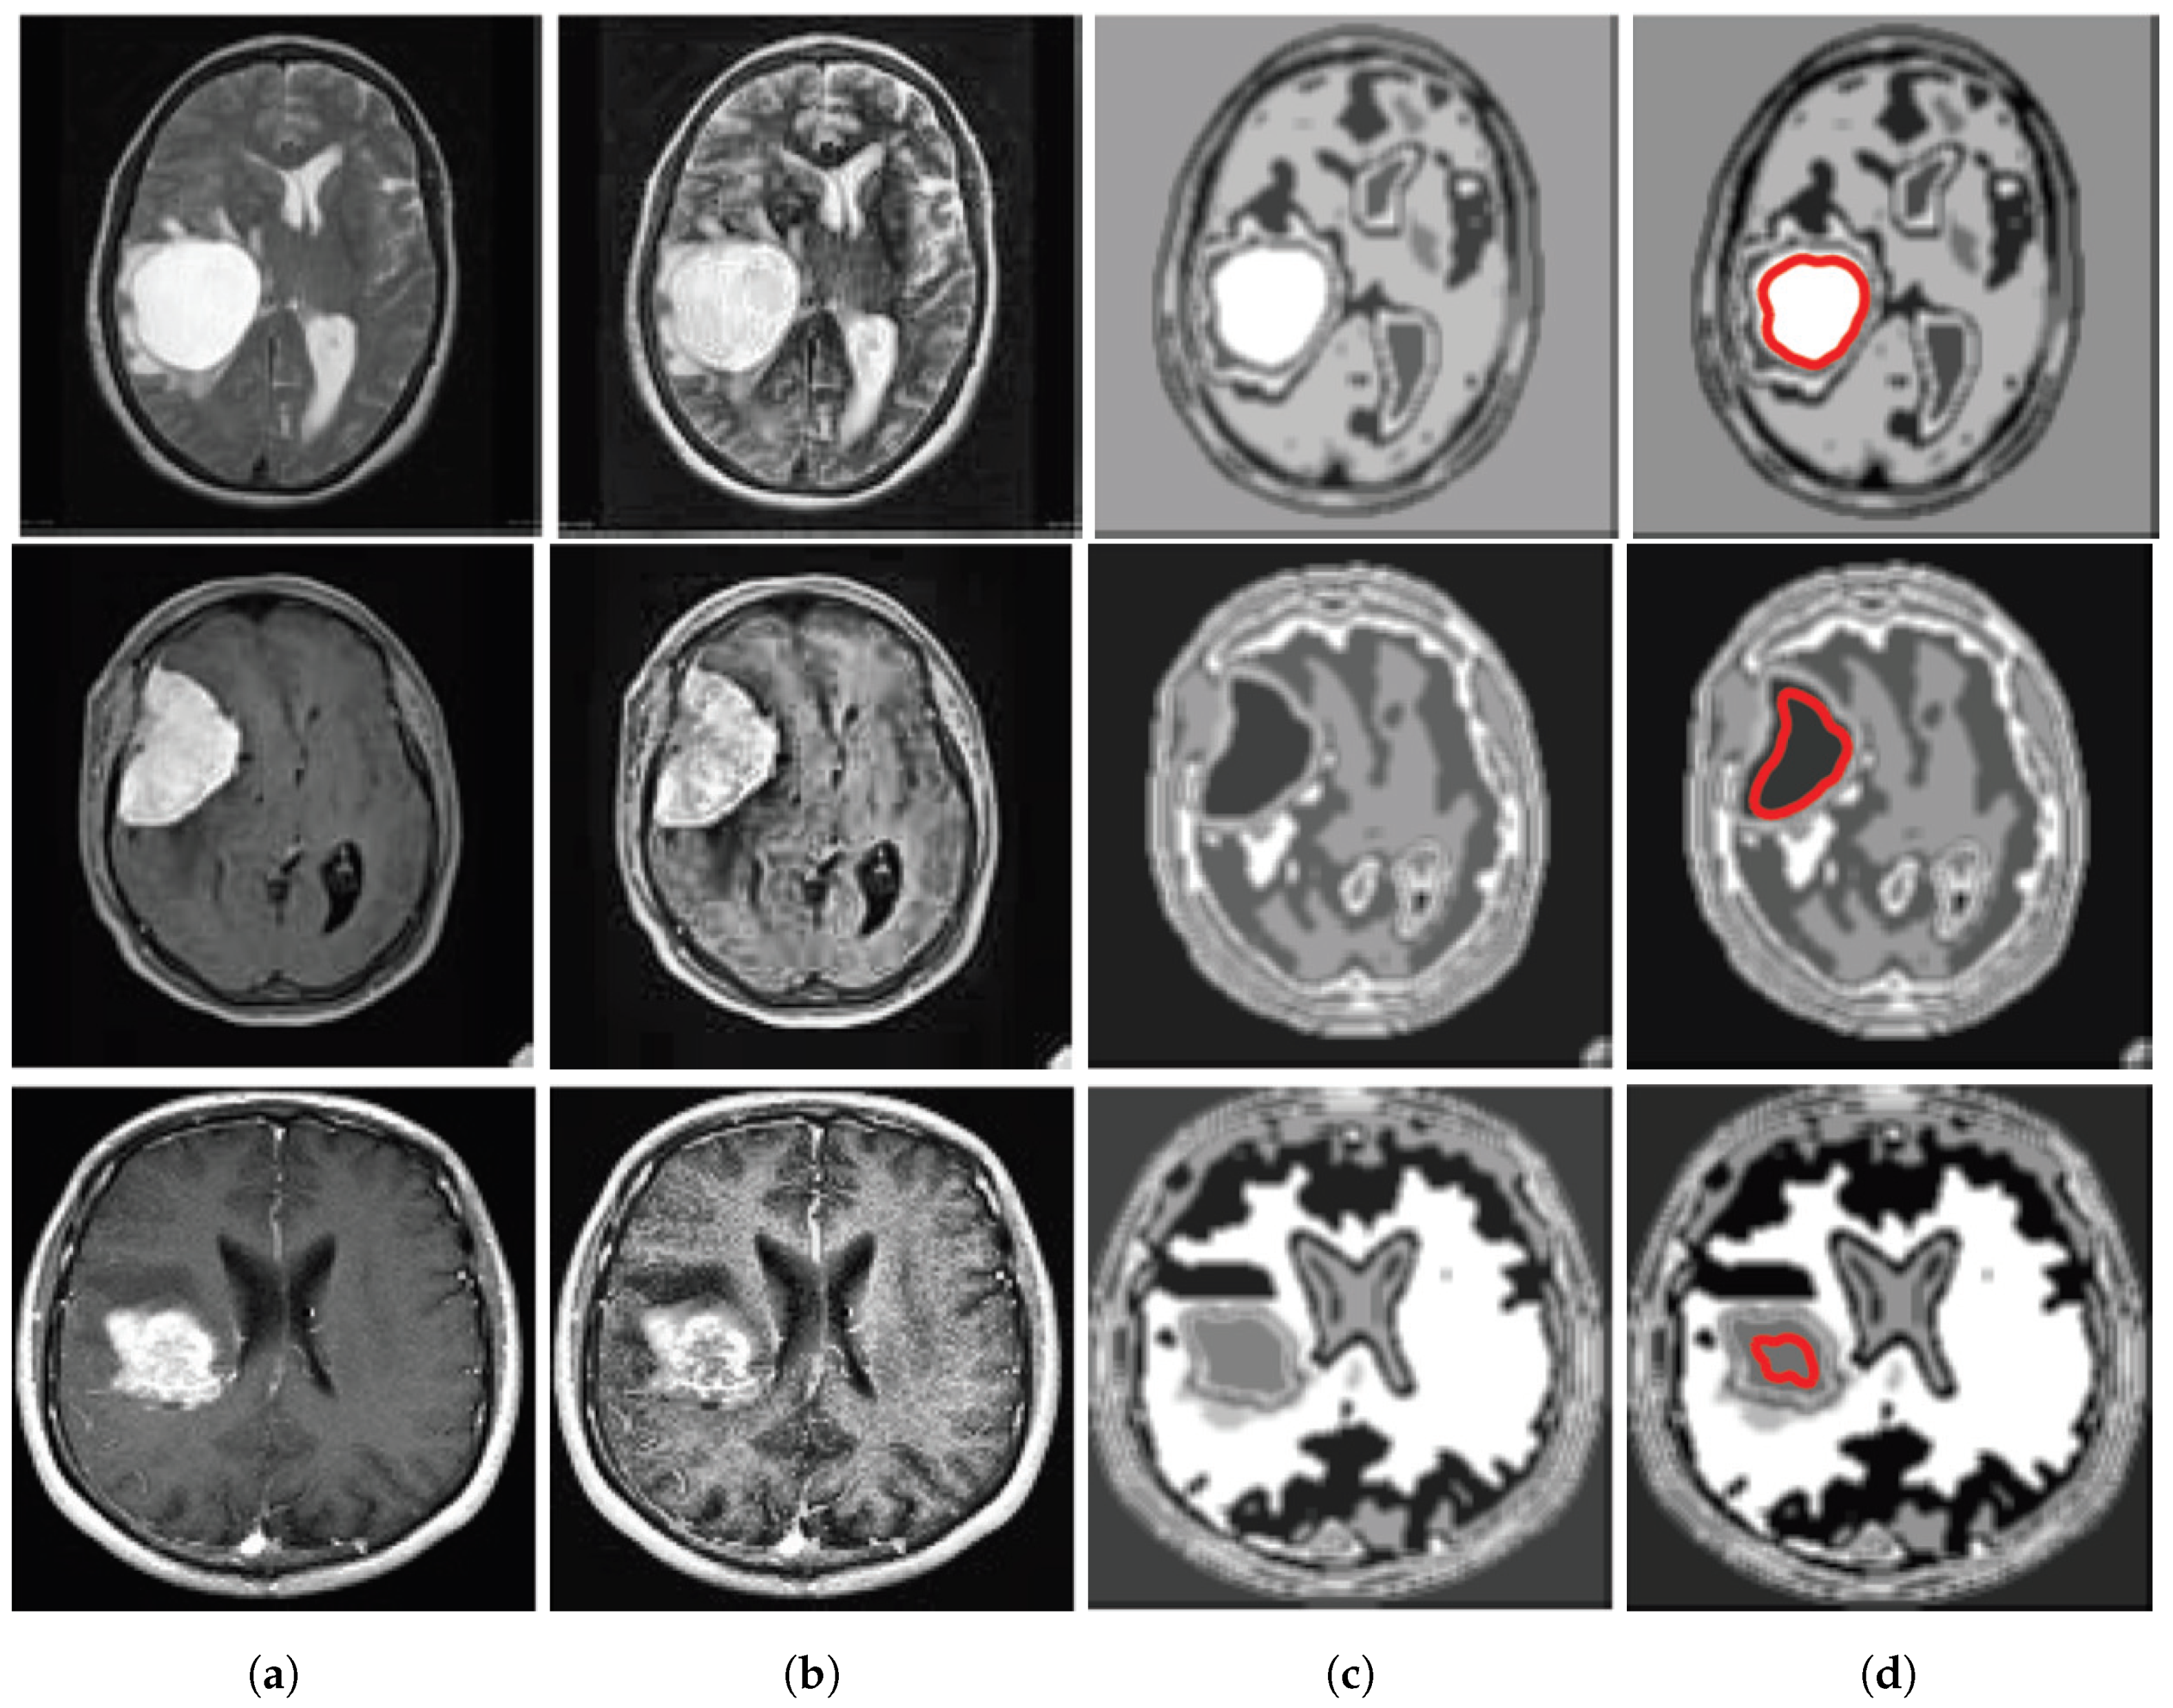

A database of 40 brain tumor images is shown in Figure 2a,b where the first 20 images are shown in Figure 2a and the next 20 images are shown in Figure 2b. The database has been made by collecting different complex brain tumor images. We collected these images from [17,18,19] and pre-processed for the betterment of application in our algorithmic program.Then, we have processed these images by MATLAB 2016(a) and made the database for final use shown in Figure 2a,b. The tumors in these images are so critical that it is too hard for the common people to detect it so easily.

Figure 2.

Database of 40 brain tumor MR image. (a) The database of first 20 brain tumor MR image. (b)The database of next 20 brain tumor MR image

Figure 5.

(a) Input images for TKFCM, (b) Segmented images from the 1st segmented algorithm (TK-means) with no. of gray level = 8, (c) Further enhancement of the segmented image, (d) Detected brain tumor images from the TKFCM.